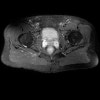

- Axial section

Axial T1 large field of view allows for evaluation of both hips simultaneously, particularly the acetabulae.

Axial PD fat suppressed is sensitive to fluid that may be present with avascular necrosis or stress fractures, while maintaining high a SNR.